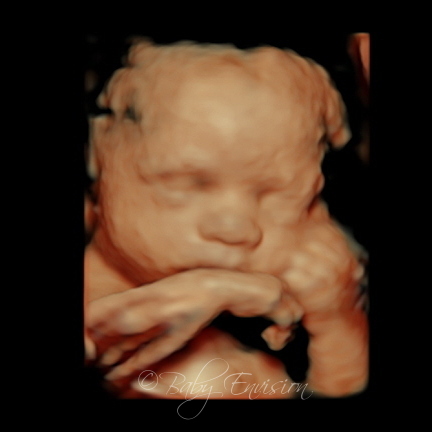

We had a growth. If you want to know your babys gender then you can book an appointment as early as 18 weeks of pregnancy. To get good pictures 3D ultrasounds are best performed between 24 and 34 weeks and the best pictures are between 27 and 32 weeks.

The best time to see your babys face and features is between 28 and 32 weeks. The best time to figure out the images of the baby is between 25 to 30 weeks. After 33 weeks the baby has slipped into your pelvis.

Medical experts agree that 24 to 32 weeks is the best time for getting 3d Ultrasound. A quick non-invasive exam Ultrasound uses high-frequency sound waves to produce real-time images. What is the best time for 3D Ultrasound.

The reason that 24 to 32 weeks is the best time for getting a 3D ultrasound is that by 33 weeks your baby has descended into your pelvis making the ability to receive clear images more. There is nothing like seeing your baby on the screen for the very first time. The following dates only apply to the best time to do your 3D4D5D ultrasound.

Around 8 glasses that hold about. However excellent pictures with 3D can be obtained at almost any time of pregnancy. At 28 weeks they are still on the skinny side and can look creepy so it may be a waste to try it that soon.